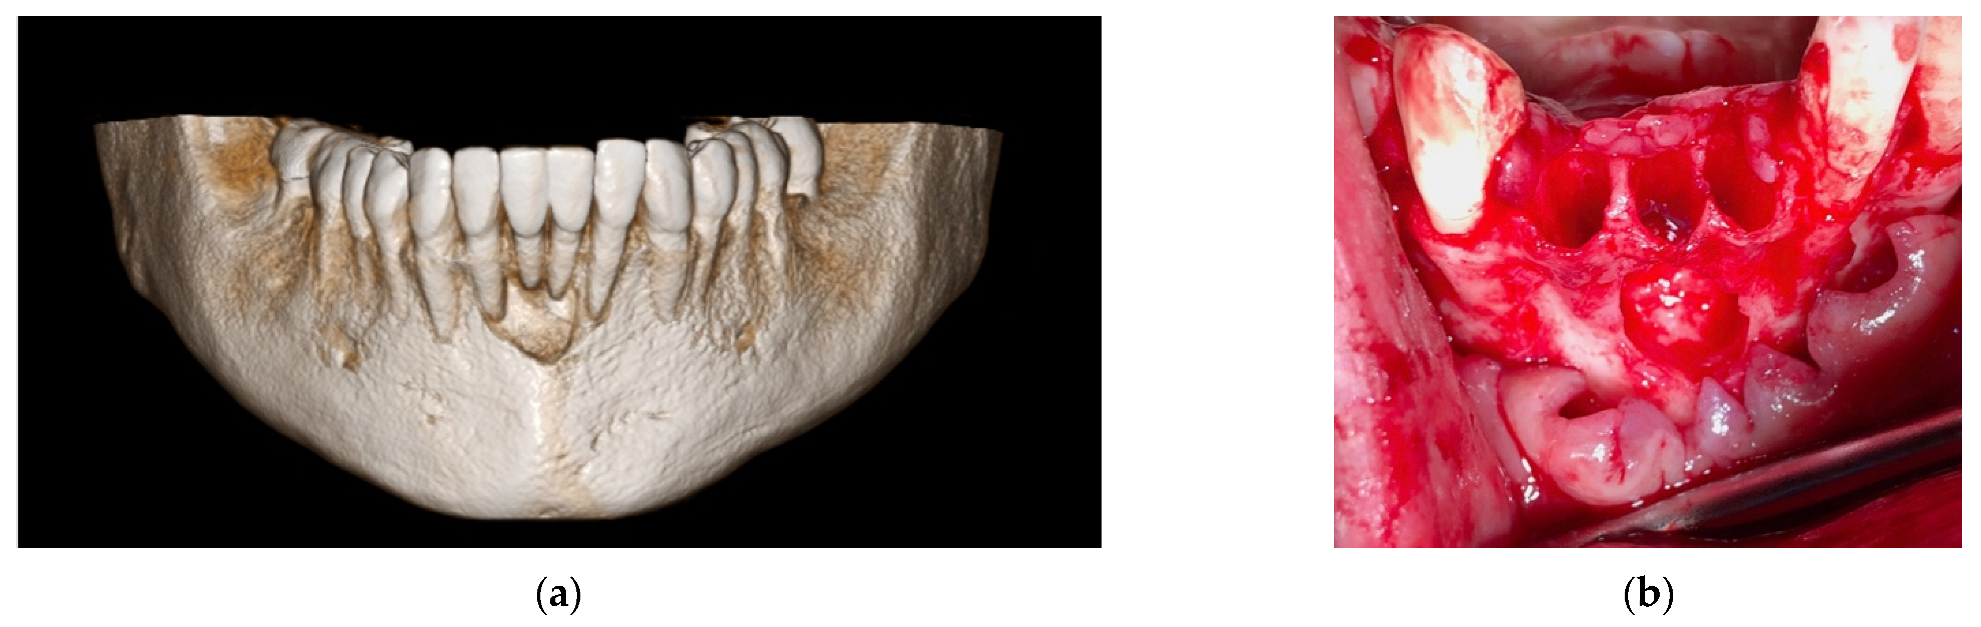

4.1. Clinical Case n.1.

4.2. Clinical Case n.2.